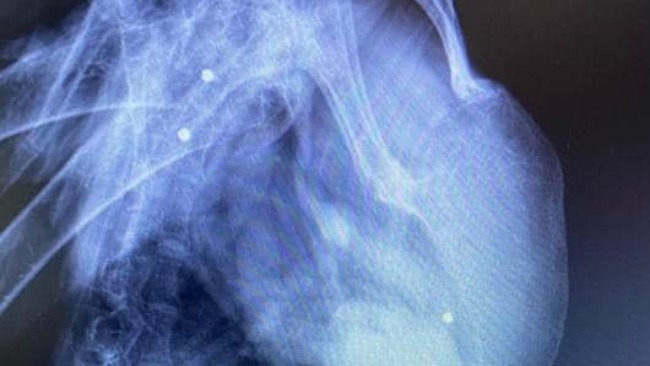

Postrzały z wiatrówek. Złamania skrzydeł. Ciężkie operacje. Długie rehabilitacje.